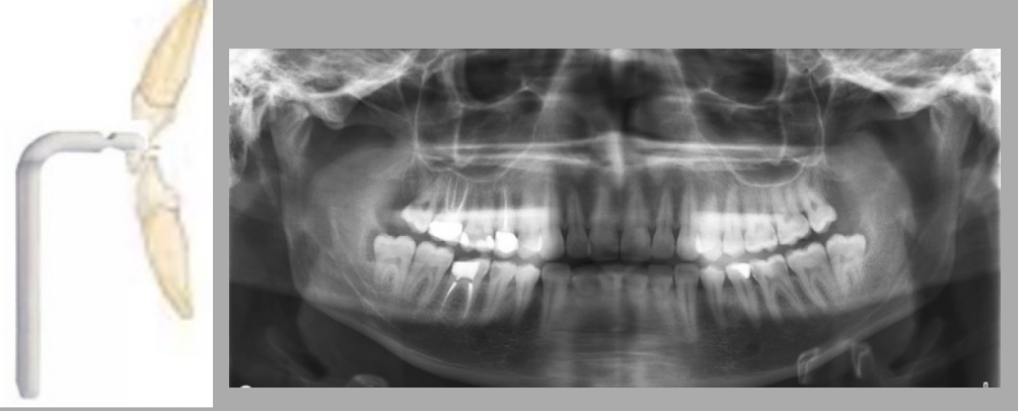

What is the most prominent error depicted in positioning of the patient by the radiographer?

A. Chin a bit too far down

B. Chin a bit too high up

C. Head too far forward

D. Head too far back